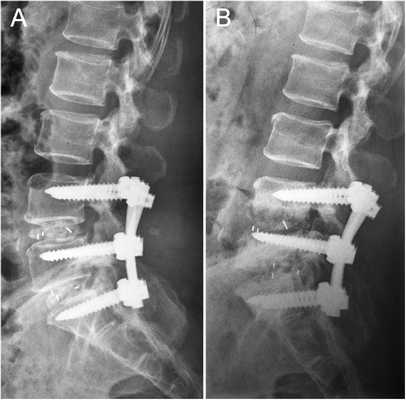

Транспедикулярная фиксация поясничного отдела позвоночника

Транспедикулярная фиксация позвоночника (далее ТПФ) является одной из самых распространенный операций в современной нейрохирургии.

Фиксация на 360 градусов

Фиксация на 270 градусов — использование только с одной стороны 2-х винтов (там, где проводилось удаление фасет-сустава и устанавливался межтеловой кейдж (т.н. TLIF)

Рентген послеоперационной перкутанной ТПФ у пациентки с множественными переломами позвоночника